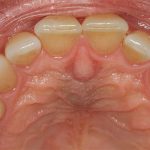

Nasopalatine duct cyst

A developmental, nonodontogenic cyst originating from embryonic remnants within the nasopalatine duct. Also known as an incisive canal cyst.